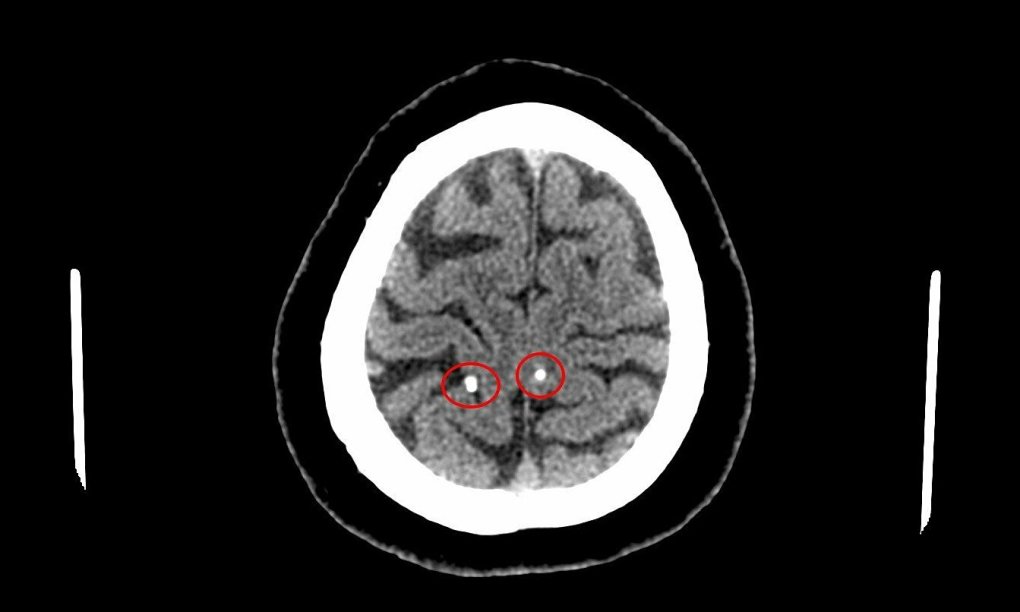

Tại khoa Chẩn đoán hình ảnh thăm dò chức năng, các bác sĩ kết luận trong sọ não bệnh nhân T. có hình ảnh nang ký sinh trùng (ấu trùng sán não - neurocysticercosis). Qua khai thác tiền sử, bệnh nhân T. cho biết ông có thói quen ăn gỏi cá.

Theo các bác sĩ, bệnh kén sán não là bệnh lý thuộc nhóm nhiễm trùng hệ thần kinh trung ương, có mức độ nguy hiểm rất cao.

Theo VnExpress, kén sán não là bệnh lý thuộc nhóm nhiễm trùng hệ thần kinh trung hương, mức độ nguy hiểm rất cao. Biểu hiện ban đầu của bệnh là nhức đầu liên tục và lan sang nhiều vùng khác. Nghiêm trọng hơn, bệnh nhân có thể xảy ra những cơn động kinh nặng nhẹ khác nhau.

Bệnh nhân có di chứng như co giật, động kinh, giảm chức năng vận động, bác sĩ có thể phải can thiệp ngoại khoa trước rồi mới điều trị bệnh ký sinh trùng. Như bệnh nhân trên, bác sĩ đánh giá chưa cần phẫu thuật, nên dùng thuốc làm chết ấu trùng sán não.